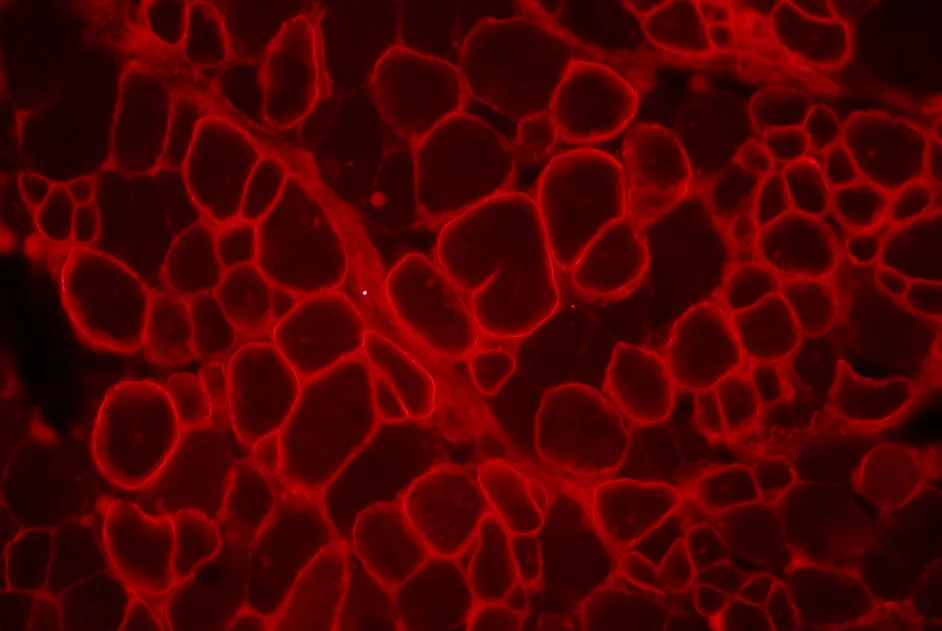

L’évolution de la myopathie de Becker semble dépendre du type de délétion dans la structure de la dystrophine.

Une équipe française, soutenue par l’AFM-Téléthon, a analysé la sévérité de la myopathie de Becker (BMD) en fonction de la structure moléculaire de la dystrophine, en collaboration avec le réseau des centres de référence neuromusculaires (CORNEMUS).

Les patients atteints de BMD présentaient dans cette étude publiée fin octobre 2014, des délétions dans une région fréquemment mutée du gène DMD : des exons 45 à 47, 45 à 48, 45 à 49 ou 45 à 51.

Les dystrophines avec des délétions 45 à 48 ou 45 à 51 présentent une structure similaire à la dystrophine normale. Ces formes de dystrophine sont associées à une évolution plus lente de la maladie que les délétions 45 à 47 ou 45 à 49.

La cardiomyopathie des patients atteints de BMD avec une délétion 45 à 47 était plus précoce que celles des patients avec une délétion 45 à 48 ou 45 à 49. En revanche, il n’y avait pas de corrélation entre les différentes délétions et la réduction de la quantité de dystrophine dans le muscle.